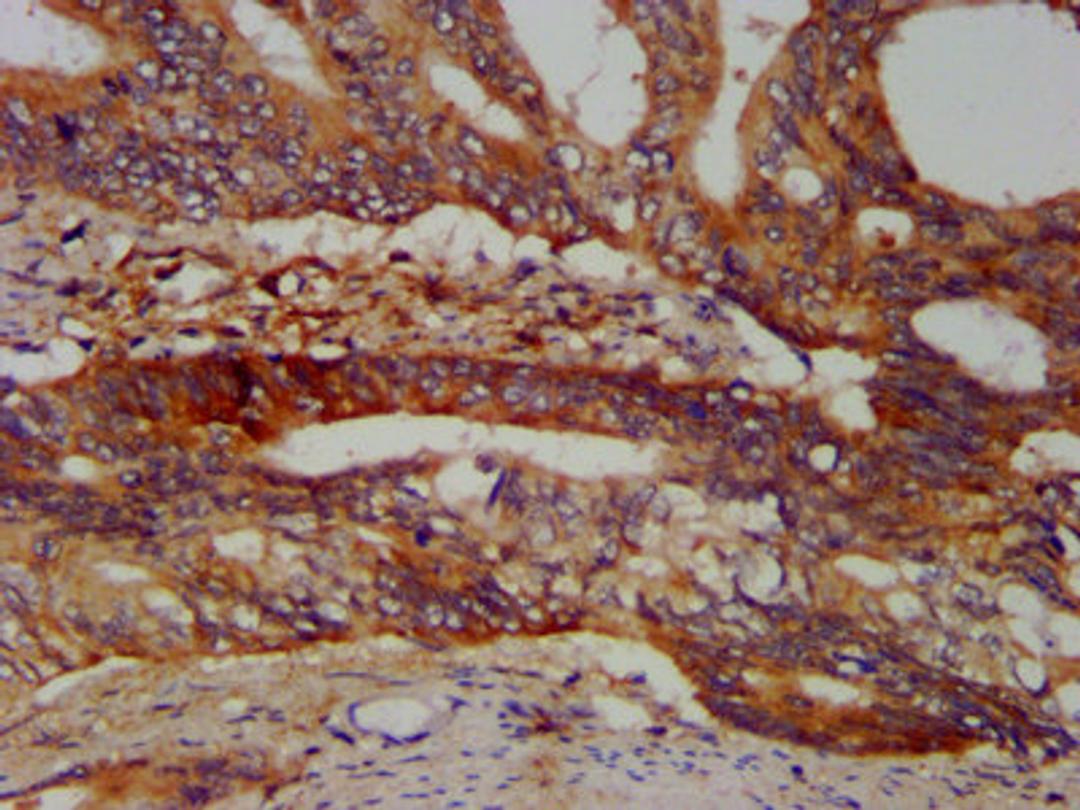

IHC image of CSB-PA897481LA01HU diluted at 1:400 and staining in paraffin-embedded human colon cancer performed on a Leica BondTM system. After dewaxing and hydration, antigen retrieval was mediated by high pressure in a citrate buffer (pH 6.0). Section was blocked with 10% normal goat serum 30min at RT. Then primary antibody (1% BSA) was incubated at 4°C overnight. The primary is detected by a biotinylated secondary antibody and visualized using an HRP conjugated SP system.